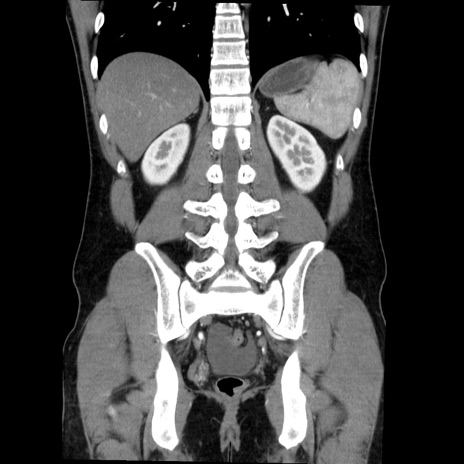

症例36(冠状断像)

【症例】20歳代 男性

【主訴】心窩部痛

【現病歴】今朝より上腹部痛あり。一旦軽快していたが再度出現したため救急要請。昨日夕に白身の魚を含む刺身を食べた。

【身体所見】BP 136/89mmHg、HR 74/min、BT 37.0℃、腹部:膨満、軟、心窩部に圧痛あり。反跳痛なし、筋性防御なし、腸雑音やや亢進あり。

【データ】WBC 17700、CRP 0.48